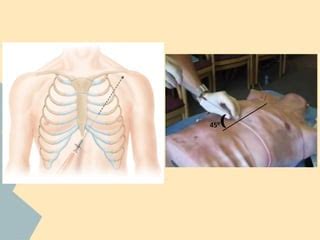

Performing pericardiocentesis is a delicate procedure that requires skilled medical professionals, typically cardiologists or cardiac surgeons. It’s usually done under sterile conditions, often in a cardiac catheterization lab or an operating room. The patient is usually positioned lying down, and the area of the chest where the needle will be inserted is cleaned and numbed with a local anesthetic. The doctor will then use imaging guidance, most commonly echocardiography (ultrasound of the heart), to visualize the pericardial sac and the fluid. This is super important for guiding the needle safely to the correct spot and avoiding injury to the heart muscle or coronary arteries. A thin, hollow needle is then carefully inserted through the chest wall, usually below the breastbone or to the side of the chest, into the pericardial space. Once the needle is in position, a syringe is attached, and the excess fluid is slowly withdrawn. The fluid is often sent to a lab for analysis to help determine the underlying cause of the effusion. In some cases, a small drainage catheter might be left in place for a short period to allow continuous drainage. The entire procedure usually takes about 30 minutes to an hour. While it’s a procedure with potential risks, like any invasive medical intervention, the benefits of relieving cardiac tamponade often far outweigh these risks when performed by experienced hands.